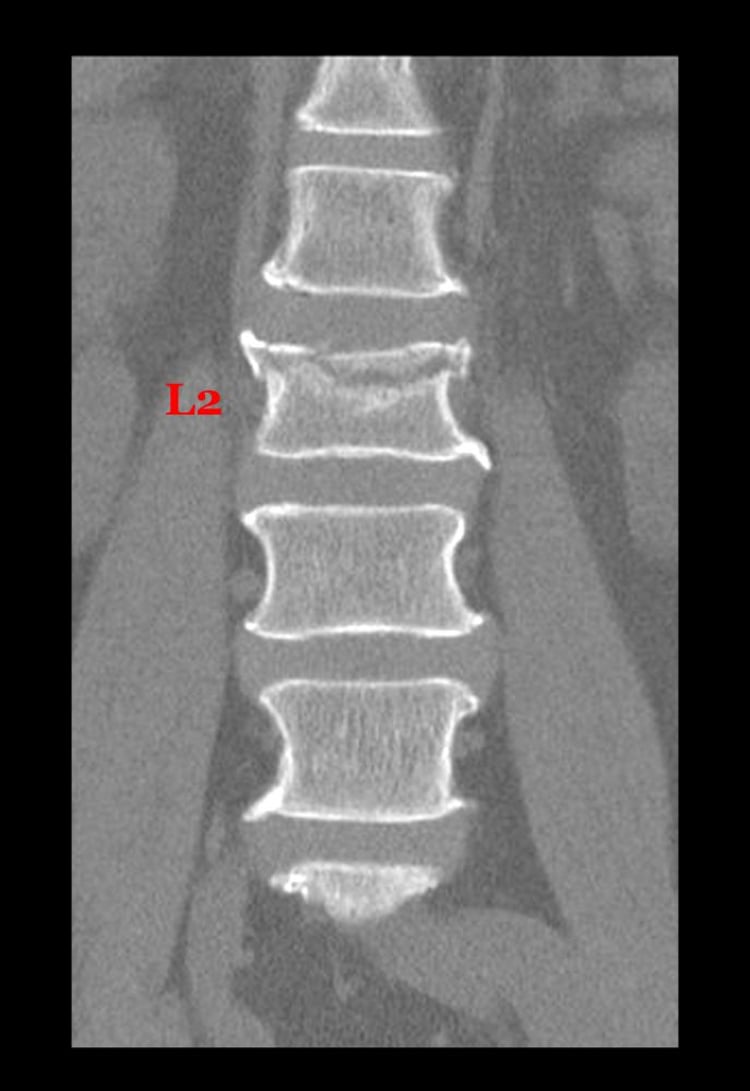

Fractura por compresión de una vértebra lumbar

Las lesiones específicas dependen del mecanismo del trausmatismo. Las lesiones en flexión pueden causar fracturas en cuña en los cuerpos vertebrales o fracturas de las apófisis espinosas. Las lesiones en flexión pueden causar una luxación bilateral de las carillas articulares o, si la fuerza se produce a nivel de las C1 o C2, una fractura de la apófisis odontoides asociada o no con subluxación atloaxoidea o occipitoatloidea. Las lesiones por rotación pueden provocar una luxación unilateral de la carilla articular. Las lesiones por extensión pueden causar la fractura del arco neural posterior. Las lesiones por compresión pueden provocar la fractura en estallido de los cuerpos vertebrales.